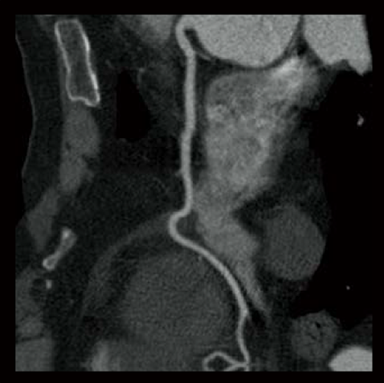

Cardio StillShot: OFF

ON